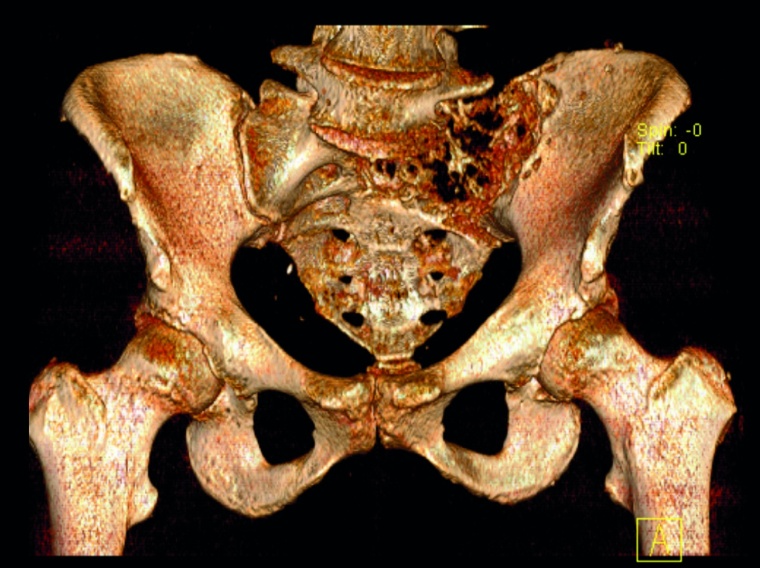

Sakrummetastasen: Stabilitätsgefährdende Metastasen am Sakrum (Abb. 3a) und am hinteren Beckenring werden zumeist mit einer mono- oder bilateralen vertebropelvinen Abstützung versorgt (Abb. 3b). Insbesondere das Os sacrum kann so aus der lasttragenden Kette herausgenommen werden. Vor allem bei Mammakarzinommetastasen kann mit der nachfolgenden Radiatio häufig eine so stabile Rekalzifikation erzielt werden (Abb. 3c), dass mitunter bei Beschwerden über dem Fixateur besonders bei schlanken Patienten eine Metallentfernung erwogen werden kann. Sollte das dorsale Os ileum mit betroffen sein (Abb. 4a) kann bei entsprechenden anatomischen Voraussetzung (Abb. 4b) auch weiter ventral auf den Beckenkamm abgestützt werden (Abb. 4c).